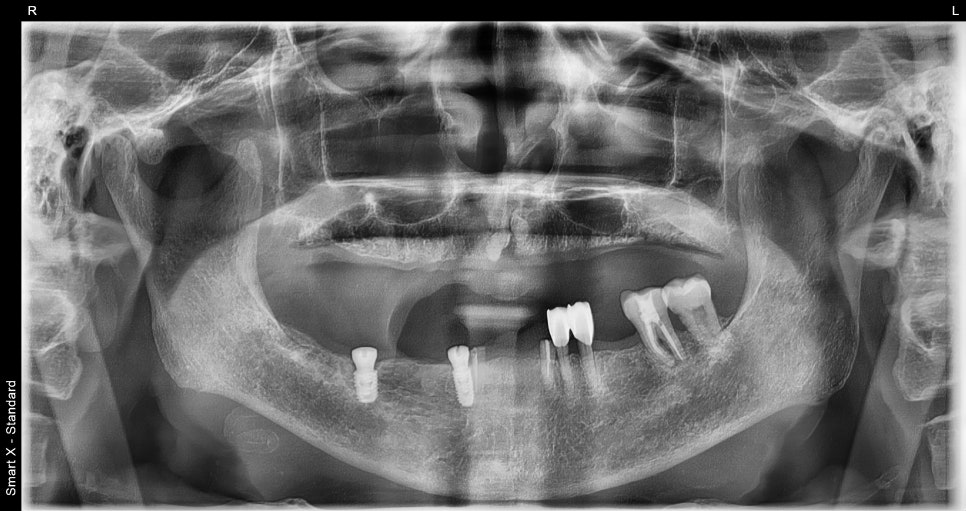

진단 및 치료 계획

진단 결과, 상악은 남아 있는 자연치들을 모두 발치 후

완전틀니 제작이 필요한 상태였습니다.

하악은 남아 있는 치아가 일부 있었지만,

안정적인 틀니 지지를 위해

보험 적용 가능한 2개의 임플란트 식립 후

부분틀니 제작을 계획했습니다.

📌 틀니 치료 전 모습

– 상악: 치아

흔들림 심하고, 기존 틀니 적합 불량

– 하악: 부분틀니 고정력 부족, 잇몸 하중 부담

하악 보험 임플란트 식립 후 의 모습